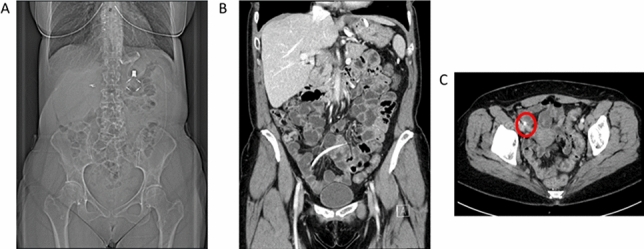

Fig. 1 Hernia sac measurements for calculating VIH (Left to right: axial, sagittal, coronal)